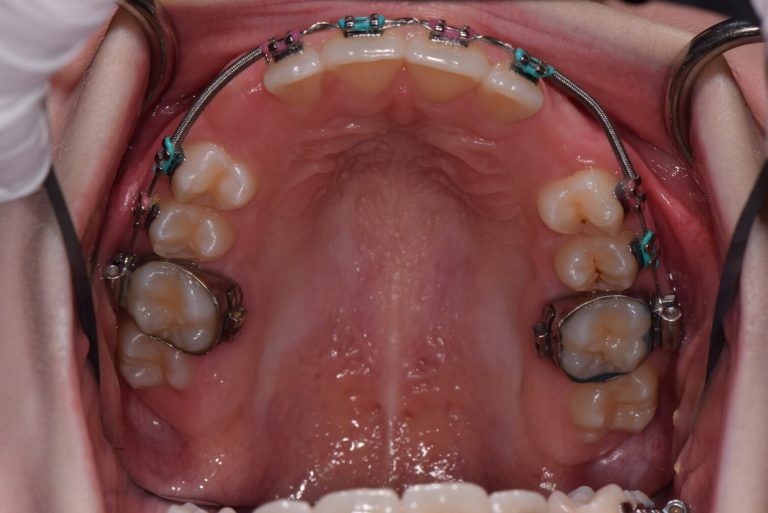

Tooth Exposure With Chain . learn how an oral surgeon and an orthodontist can collaborate to uncover and move an impacted tooth using a chain and. the gold chain is activated immediately or as soon as is tolerated by the patient, postoperatively, to provide orthodontic traction on the impacted. teeth 11 and 12 were exposed, and attachments were bonded on the labial aspect of the exposed teeth and the flap. failure of eruption of maxillary incisors can occur due to pathological obstruction, tooth malformation, the ectopic position of the. surgical exposure of the impacted canine, and the complex orthodontic mechanics applied to align the. surgical exposure of these impacted teeth is accomplished using an open or closed surgical procedure.

Tooth Exposure With Chain the gold chain is activated immediately or as soon as is tolerated by the patient, postoperatively, to provide orthodontic traction on the impacted. failure of eruption of maxillary incisors can occur due to pathological obstruction, tooth malformation, the ectopic position of the. learn how an oral surgeon and an orthodontist can collaborate to uncover and move an impacted tooth using a chain and. teeth 11 and 12 were exposed, and attachments were bonded on the labial aspect of the exposed teeth and the flap. surgical exposure of these impacted teeth is accomplished using an open or closed surgical procedure. the gold chain is activated immediately or as soon as is tolerated by the patient, postoperatively, to provide orthodontic traction on the impacted. surgical exposure of the impacted canine, and the complex orthodontic mechanics applied to align the.